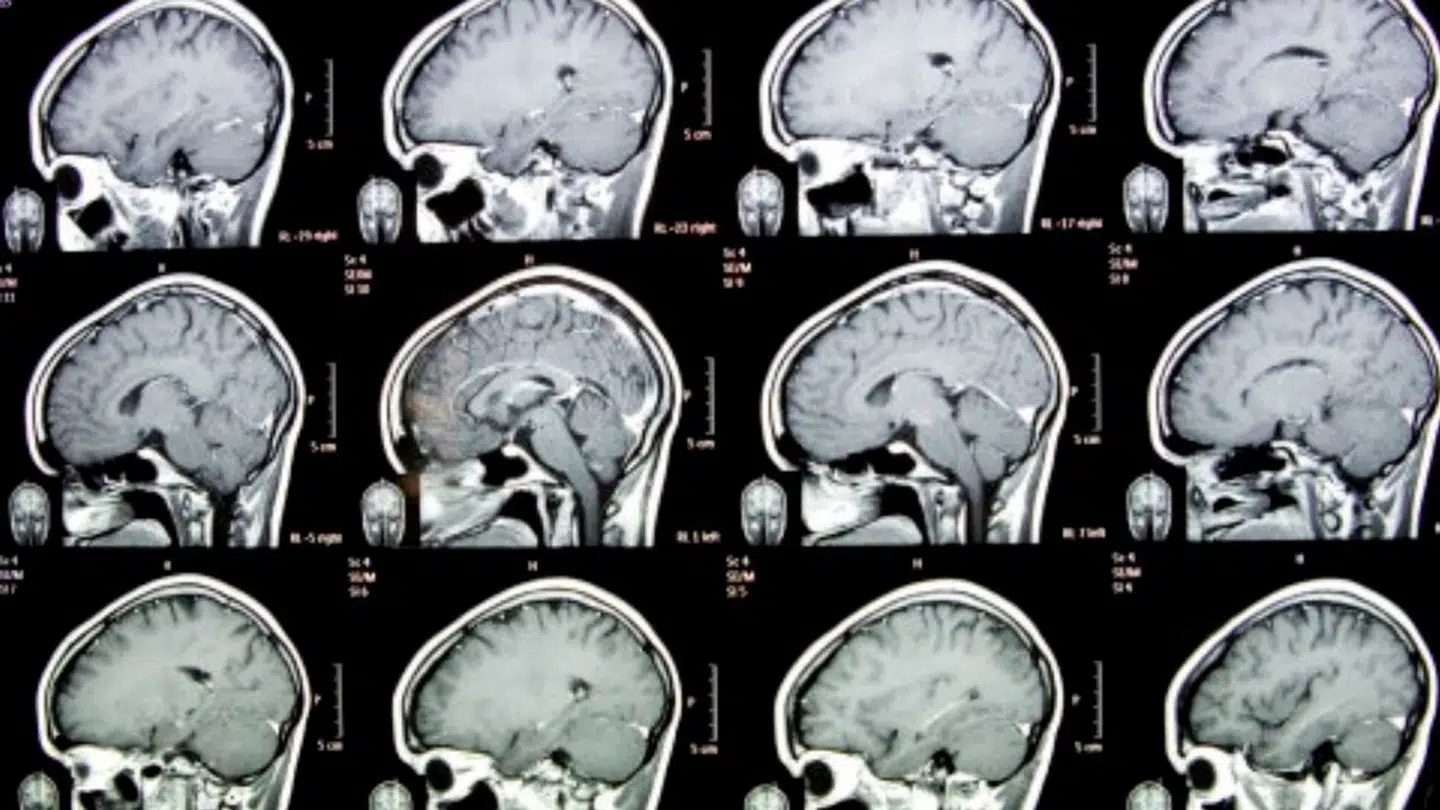

Nu spår nyt studie, at endnu en alvorlig og uhelbredelig sygdom kan få kamp til stregen af samme type af medicin.